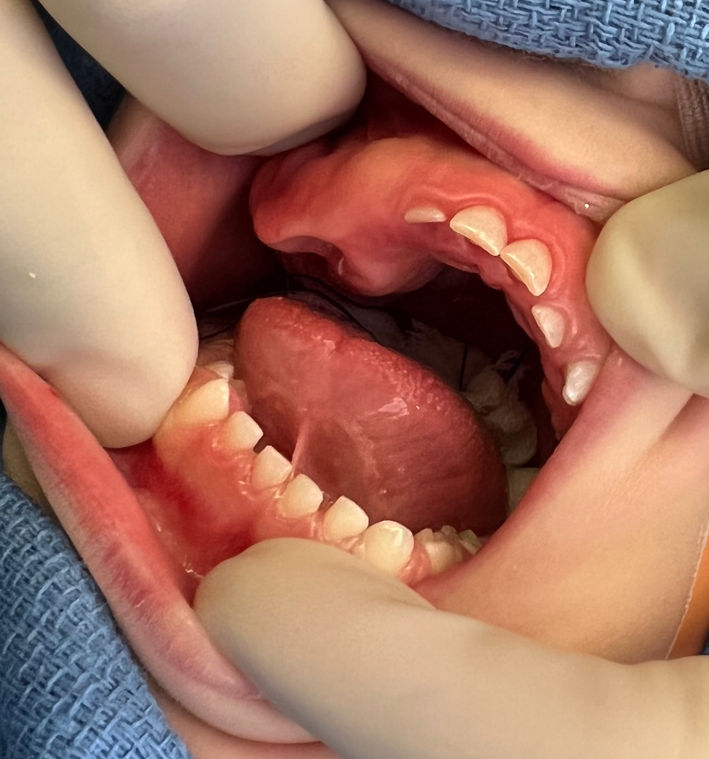

1-month-old girl with mandibular incisor

A 1-month-old girl with a mobile primary mandibular incisor.